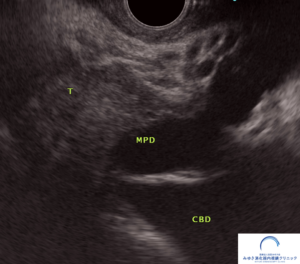

MRIの2日後には、超音波内視鏡検査を行いました。

超音波内視鏡検査でも、MRIと同様に膵頭部に腫瘍を認め、胆管と膵管は閉塞しています。

<超音波内視鏡>

T:腫瘍、MPD:主膵管、CBD:総胆管